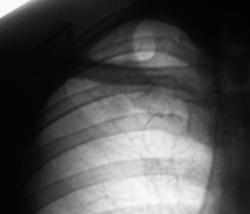

Флюорограмма 2007 год.

1._F-graf..JPG